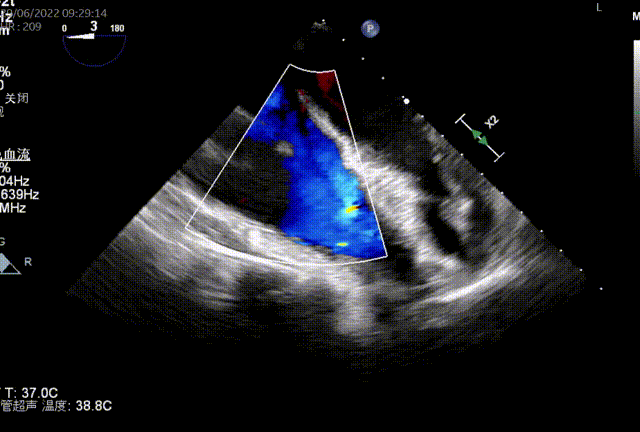

图2:术中TEE

同时其夹子系统继承于申淇淇麟®-经导管二尖瓣夹及可操控导引导管系统优秀设计,具备四个不同型号的夹子及瓣叶分开捕获能力,从而适用于更加复杂多变的三尖瓣解剖。因该患者三尖瓣反流束较宽,瓣叶存在较宽的关闭裂隙,术中很好的利用了瓣叶分开捕获的功能,于前隔瓣区域行瓣膜缘对缘修复。植入一枚长宽夹子后,术后即刻患者反流减至轻度。患者术后恢复良好,出院前TTE提示三尖瓣轻度反流。